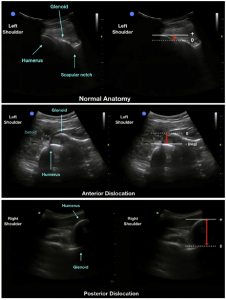

Ultrasonographic images of the shoulder girdle, using a curvilinear probe demonstrating the normal anatomy of the left glenohumeral joint (A), a left anterior dislocation of the shoulder with humeral head displaced anterior to the glenoid (B), and a right posterior shoulder dislocation with the humerus displaced posterior to the glenoid (C). The adjacent images correspond to the measurement of the glenohumeral distance, indicated by the red arrows.